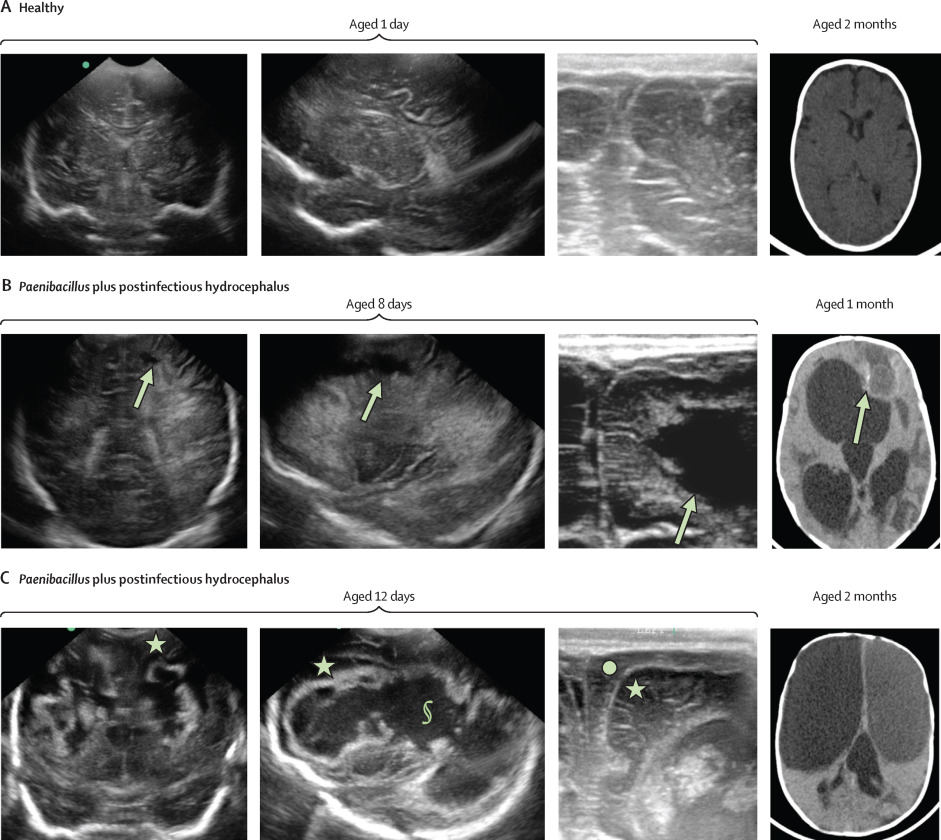

脑积水是一种严重的神经系统疾病,是由于脑室深处的脑脊液异常积聚造成的。过量的脑脊液会导致脑室扩张,对大脑组织造成有害的压力。这种疾病可能是先天性的,也可能是在脑部感染或出血后出现。

到 2020 年,希夫的团队集合了哥伦比亚大学和宾夕法尼亚州立大学的研究人员,通过基因组测序发现,一种以前被认为在脑脊液中无害的生物--硫氨基溶解巴氏杆菌--正在乌干达脑积水婴儿的大脑中游动。研究人员偶然发现了一种成功培育其中一些菌株的方法--用血液培养瓶来培养脑脊液。这让他们发现,这种生物对用于治疗患病婴儿的一线抗生素具有抗药性。他们还发现,这些非洲菌株感染了一种致命性很强的毒素。2020 年,他们在《科学转化医学》(Science Translational Medicine)杂志上发表了这些测序和培养结果。

在 400 例婴儿脑积水病例中,44% 的感染后病例通过 PCR 确认感染了巴氏拟杆菌。当研究小组对感染后出现脑积水的败血症新生儿样本进行 PCR 检测时,发现了导致新生儿感染的相同细菌,并且在治疗后,当他们在数周或数月后因脑积水导致头部增大而再次接受治疗时,仍然存在相同的细菌。

《柳叶刀微生物》论文的共同第一作者、博士后研究员 Christine Hehnly 博士说:"我们首次描述了从新生儿期感染到婴儿感染后脑积水的发展过程,使我们能够指导关键的诊断和干预措施,防止感染后脑积水带来的破坏性脑损伤。"